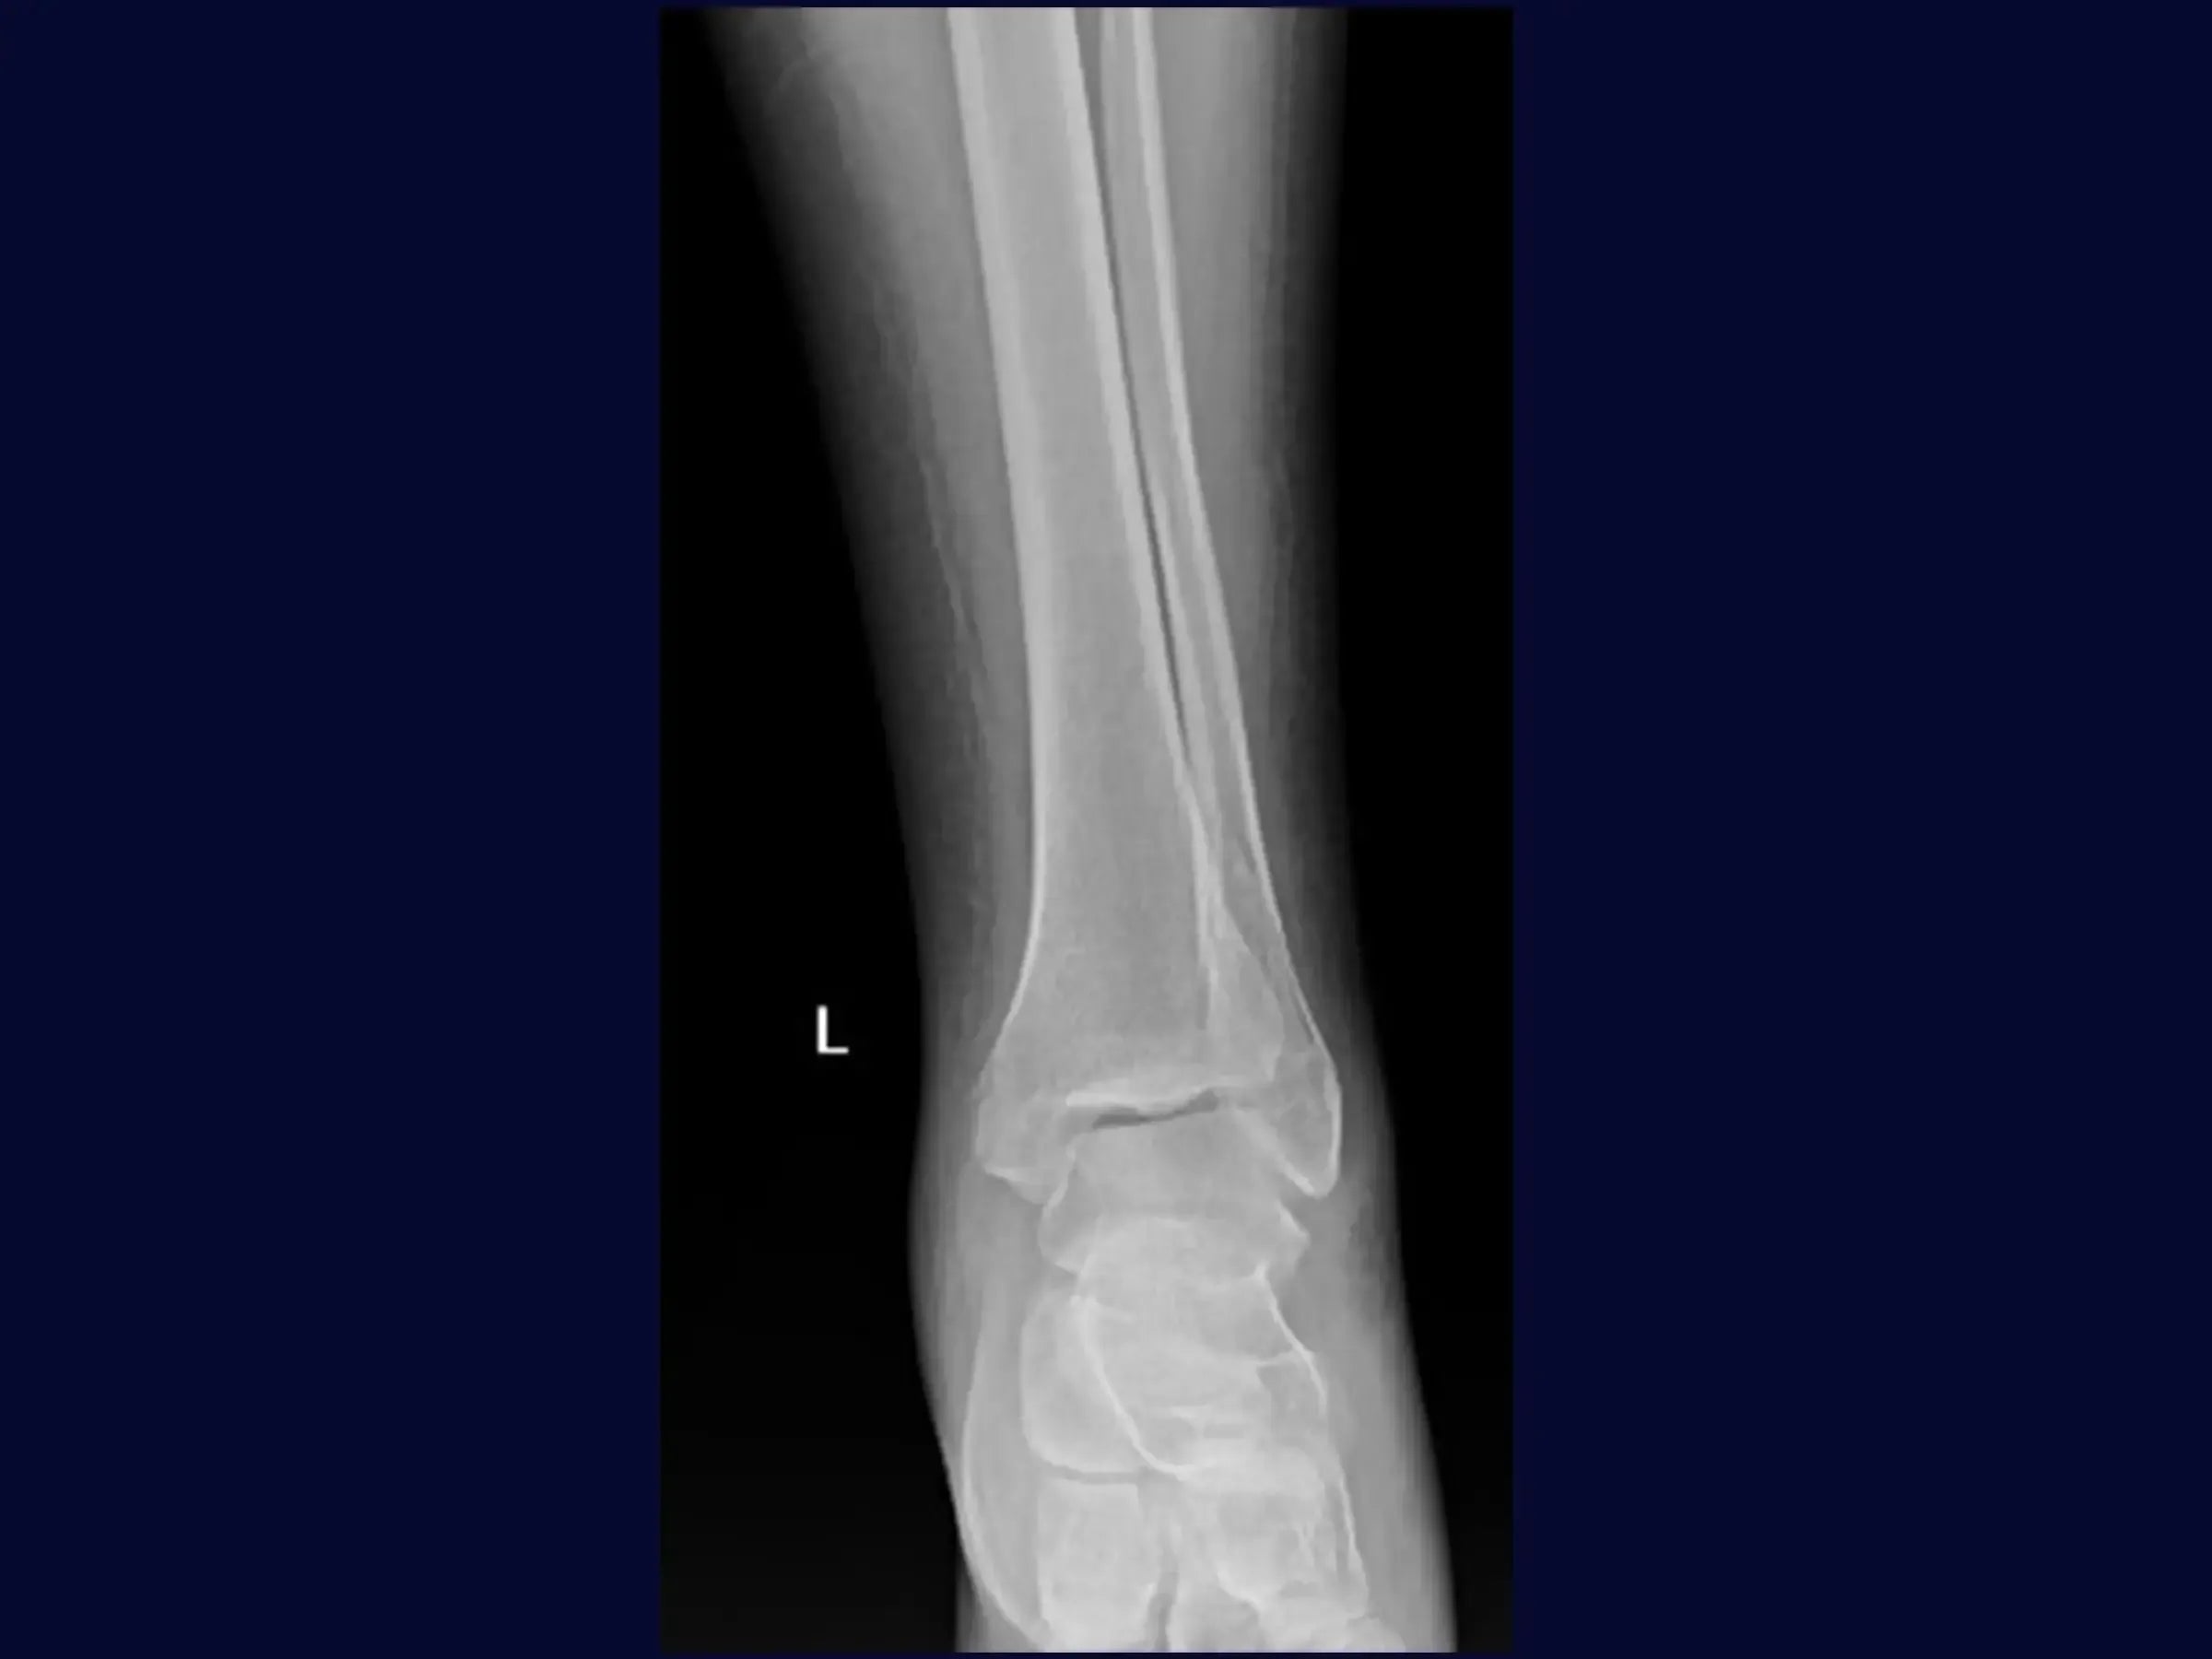

Aprimore o manejo de fraturas isoladas do maléolo lateral, especialmente as com componente multifragmentar. Este treinamento oferece uma imersão técnica na osteossíntese com placa posterior como estratégia adaptativa, apresentada em vídeo de alta resolução sob a perspectiva cirúrgica, focando na flexibilidade do planejamento intraoperatório e na mobilidade precoce.

- Tratamento cirúrgico de fraturas isoladas do maléolo lateral com componente fragmentar.

- Acesso Cirúrgico Lateral Formal: Garantia de campo limpo e identificação precisa da fratura.

- Redução Anatômica por "Dentes da Fratura": Técnica para identificar e coaptar os fragmentos com precisão.